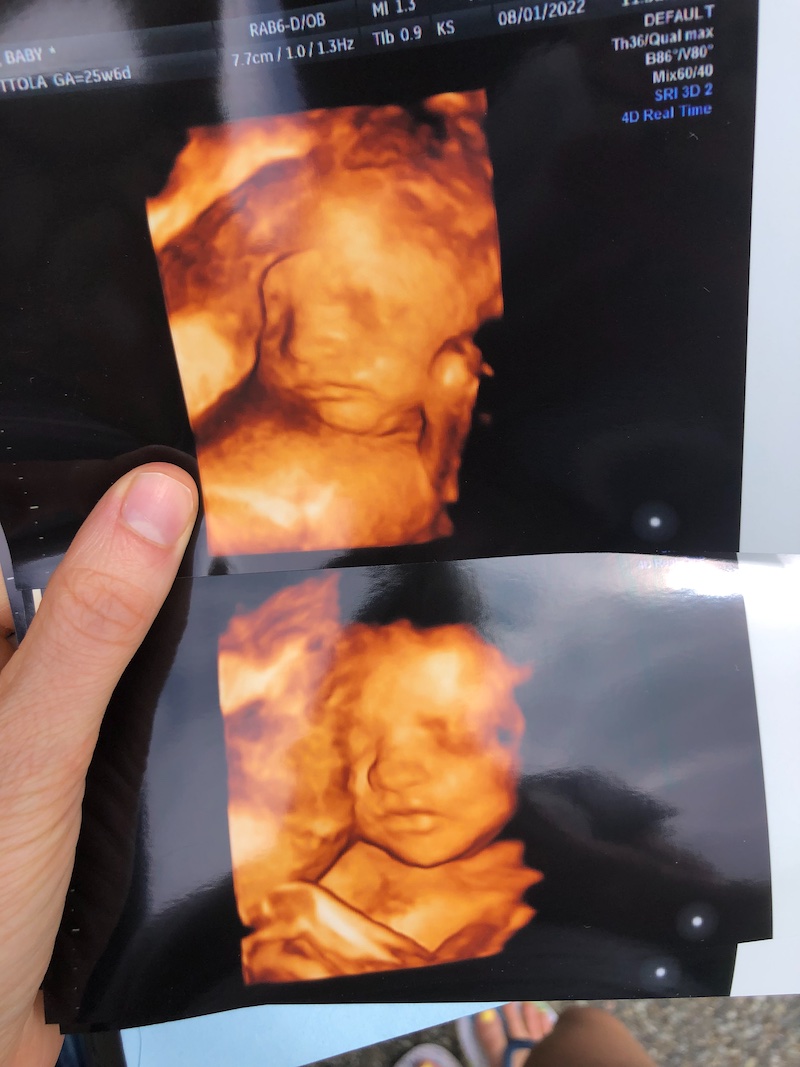

I scheduled an ultrasound at a boutique ultrasound place the day after the bleeding scare because I wanted to see baby and make sure he was okay. The ultrasound was 4D and wow was it amazing! Worth every penny for paying about $100 out of pocket. I saw his adorable little face and felt so much peace about how he’s doing. God is good!

The scan pictures are so crazy good!

Its amazing to see all the face features!

I love when you post your pregnancy journal!! The 4d US is incredible- He looks just like Sadie (in my opinion).

Aww, thank you so much! I was so happy with those ultrasound pictures!! I agree, he looks a lot like his big sis!